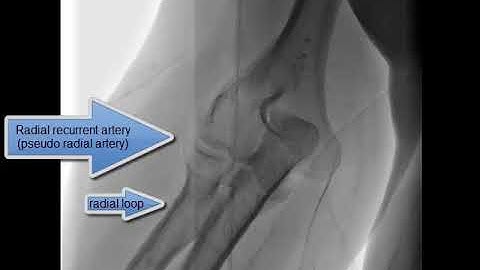

Radial artery loop: management